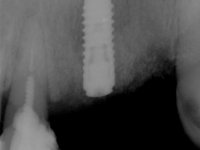

Foram feitas as extrações das raízes dos dentes 2.1 e 2.2 porque estavam a incomodar. Após 3 meses de cicatrização fez-se o exame imagiológico e estudo implantar para colocação do implante no local do 2.1.Foi colocado um implante de 4.1mm de diâmetro por 10mm de altura, colocado ao nível ósseo. Passados 2 meses após a cirurgia implantar, foi feita a segunda cirurgia para colocação de um parafuso de cicatrização. Foi feita a impressão ao implante com técnica de moldeira aberta com silicone de dupla viscosidade um mês após. No laboratório foi confecionada uma infraestrutura metálica para uma ponte de 2 elementos aparafusada ao implante. Esta infraestrutura apresentava 2 apoios palatinos para ajudar a estabilizar os dentes 1.1 e 2.3 a recuperar do traumatismo. Recuperados os dentes, os apoios poderiam ser retirados. Esta peça apresentava uma conexão interna ao implante com sistema anti-rotacional. A prova da infraestrutura foi feita em boca sendo o seu correto ajuste verificado com controle imagiológico. No revestimento da infraestrutura foi utilizada cerâmica de tonalidade coronária e gengival. Depois de verificada em boca e aprovada pelo paciente a ponte foi apertada definitivamente e o orifício de acesso obturado.

6 meses após a colocação da ponte, o paciente sofre um novo traumatismo comprometendo a viabilidade dos dentes 1.2 e 1.1. Foi realizada uma prótese removível acrílica para reabilitar provisoriamente o paciente enquanto foram extraídos os dentes 1.2 e 1.1 e foi colocado o implante no local do dente 1.1. Passados 3 meses foi realizada uma impressão ao implante colocado no 1.1 e simultaneamente foi feito um arrasto da ponte dos dentes 2.1 e 2.2. Para esse efeito no implante 2.1 foi utilizado um parafuso de uma peça de transferência. Dessa forma conseguiu-se impressionar corretamente a arquitetura gengival do sector antero-superior. O objetivo era simultaneamente impressionar corretamente esta zona e aproveitar a estrutura metálica desta ponte para confecionar a nova ponte de 4 elementos. Foi colocado um parafuso de cicatrização no implante 2.1 e foram acrescentados os dentes 2.1 e 2.2 na prótese removível. Com perícia laboratorial foi criada uma nova infraestrutura metálica de 4 elementos assente nos implantes 1.1 e 2.1 e com os elementos pônticos suspensos 1.2 e 2.2. No implante 2.1 manteve-se a conexão interna ao implante no implante 1.1 optou-se por uma peça intermédia facilitando a inserção da infraestrutura. A nova infraestrutura foi verificada em boca. Como pode ter havido alguma alteração da arquitetura gengival com a remoção da ponte e colocação do parafuso de cicatrização no 2.1, foi feita uma chave de silicone para permitir uma impressão de arrasto da infraestrutura metálica. Uma nova gengiva artificial foi realizada no modelo de trabalho de acordo com esta impressão de arrasto. Foi colocada cerâmica de tonalidade coronária e gengival. A peça protética foi aparafusada lentamente em boca para permitir uma adaptação dos tecidos moles. Após o correto assentamento e verificação imagiológica a ponte foi definitivamente apertada em boca e os orifícios de acesso obturados. Independentemente dos infortúnios que o paciente teve, pude ter a satisfação de o ver contente com esta reabilitação.